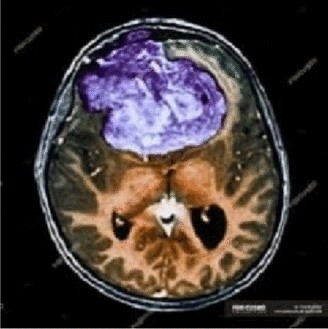

Cipher image 2

View full size image